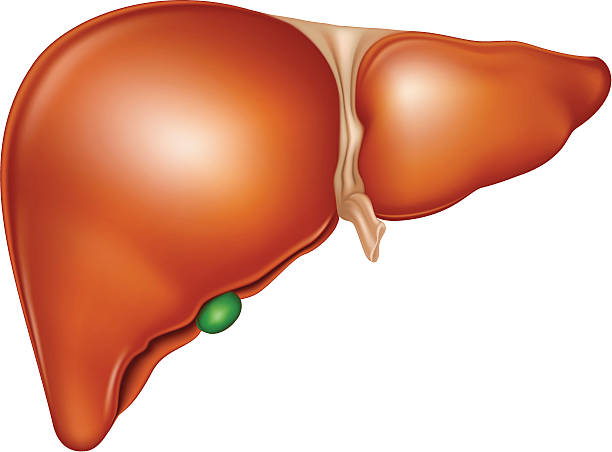

El hígado humano constituye una estructura anatómica y funcional de extraordinaria complejidad, cuya singularidad radica tanto en su tamaño como en la diversidad de procesos bioquímicos que integra de manera simultánea. En el adulto sano, su masa oscila aproximadamente entre 1.2 y 1.5 kilogramos, lo que lo posiciona como el órgano sólido más voluminoso del organismo. Esta magnitud no es arbitraria, sino que refleja la enorme carga metabólica que asume, al actuar como centro integrador del metabolismo intermediario, de la detoxificación y de la regulación sistémica. La localización subdiafragmática en el cuadrante superior derecho del abdomen no solo responde a un arreglo anatómico, sino que optimiza la conexión directa con el tracto gastrointestinal mediante la circulación portal, permitiendo el procesamiento inmediato de los nutrientes absorbidos.

La vascularización hepática presenta una organización única en el organismo humano, caracterizada por la convergencia de dos sistemas sanguíneos distintos. La arteria hepática aporta sangre rica en oxígeno, mientras que la vena porta hepática transporta sangre cargada de nutrientes, metabolitos y posibles toxinas provenientes del intestino. Este doble suministro permite que los hepatocitos estén expuestos de manera directa a los productos de la digestión, lo que facilita su procesamiento inmediato. La arquitectura sinusoidal del hígado, compuesta por capilares especializados de endotelio fenestrado, favorece el intercambio eficiente de sustancias entre la sangre y las células hepáticas.